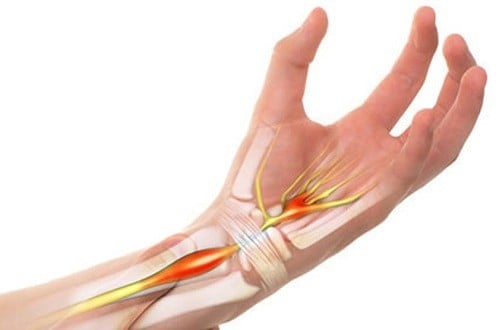

Hội chứng ống cổ tay  – nguyên nhân và cách điều trị

Hội chứng ống cổ tay là một bệnh lý phổ biến, có thể gặp ở mọi lứa tuổi tuy nhiên gặp nhiều nhất ở người từ 45-60. Tỷ lệ mắc bệnh ở nữ gấp 3 lần nam giới. Vậy nguyên nhân nào dẫn đến hội chứng ống cổ tay, triệu chứng bệnh như thế nào? […]